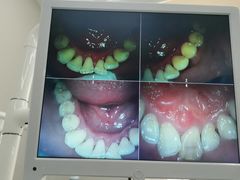

• -牙博士口腔品牌连锁(杨浦店)

闪闪 | 22-07-28

报错